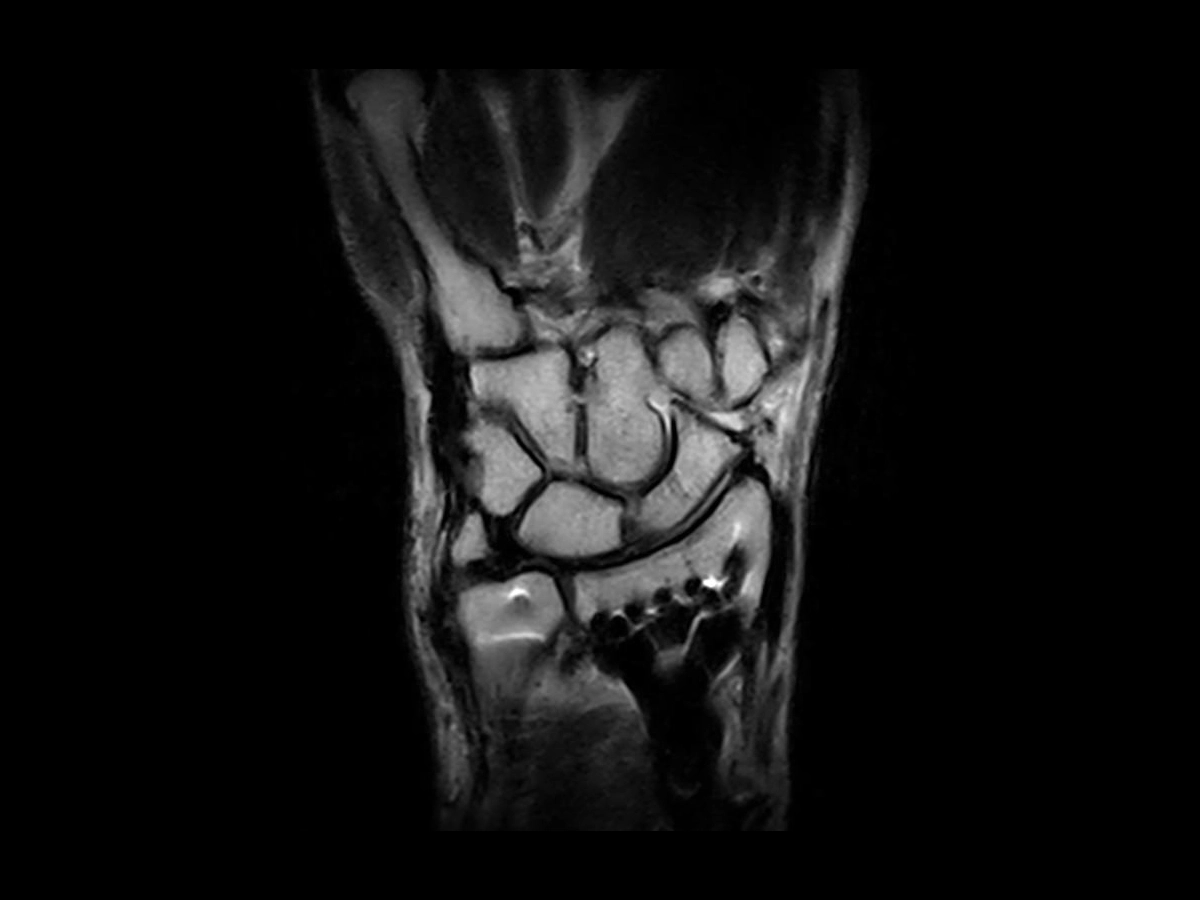

SPED

BETTER - MORE VERSATILE

SPED is the Spin Echo fat-water separation sequence based on the Dixon technique generating a contrast similar to a FATSAT type of scan. SPED is therefore a valuable addition to the current range of fat suppression sequences.

Main characteristics:

• SPED is robust and less prone to artefacts.

• Morphological information and Fat-Suppression images.

• Possibility to achieve different contrast, T1 and PD based on the chosen TR.

• Efficient in presence of metal implants.